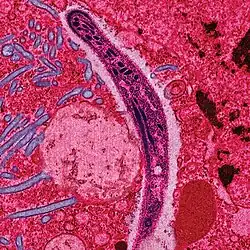

Apicomplexa Levine, 1970 è un subphylum di protozoi che comprende organismi endoparassiti, composti in gran parte da un'unica cellula, e dotati di strutture adatte a penetrare nelle cellule di altri esseri viventi e nutrirsene. Il loro nome (dal latino apex (sommità) e complexus (proteso)) deriva dal cosiddetto complesso apicale, una struttura cellulare fatta di fibrille, microtubuli o altri organelli cellulari con il quale questi organismi si introducono nelle cellule degli animali ospiti. In questo insieme sono raggruppate due classi, Sporozoea, suddivisa a sua volta in tre sottoclassi Gregarinia, Coccidea e Hematozoa, e la classe Perkinsea.

Internamente la caratteristica più importante è data sicuramente dal complesso apicale posto nella parte anteriore ed è composto di cinque parti. Da uno o più anelli polari, da un conoide posto all'interno dell'anello polare e composto da vari microtubuli a forma di serpentina, da una serie di micronemi, ovvero organelli di forma tubulare che si sviluppano longitudinalmente, da altri organelli detti roptrie e infine da microtubuli subpellicolari che partono dall'anello polare e si dipanano verso l'interno del protozoo. Le funzioni specifiche di ogni organello che compone il complesso apicale sono tuttavia ancora in fase di studio e restano sconosciute[1]. Tuttavia si ipotizza che le roptrie siano organi addetti alla secrezione di particolari sostanze che collaborano insieme agli altri organelli del complesso apicale per la penetrazione delle cellule dell'organismo ospite di questi parassiti.